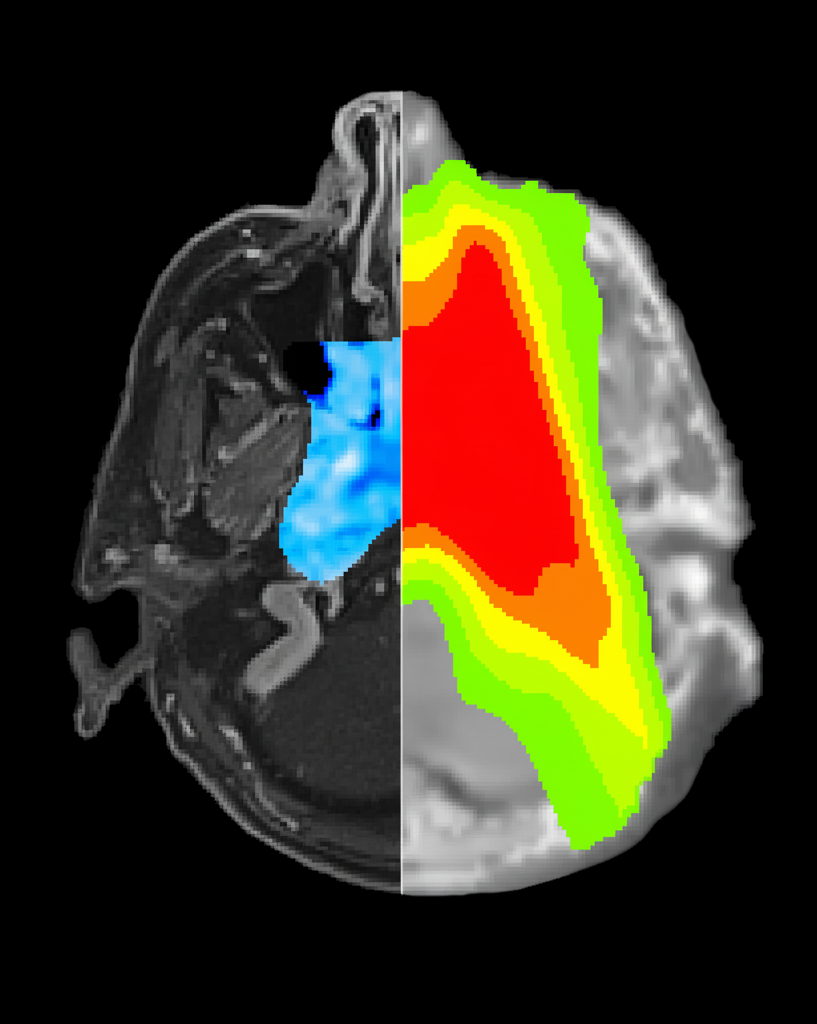

Les membres du laboratoire élisent chaque année la plus belle image

créée au sein du laboratoire au cours de l'année écoulée. L'image 2025

lauréate est issue de travaux menés en oncologie pour la plannification

du traitement. La partie à gauche correspond à une image par résonance

magnétique pondérée T1 après injection de gadolinium, avec superposition

de la carte de la composante de diffusion pure. La partie de droite

représente une tomodensitométrie synthétique dérivée de l'imagerie par

résonance magnétique, avec superposition de la distribution des isodoses

pour la radiothérapie, représentée par un code couleur.